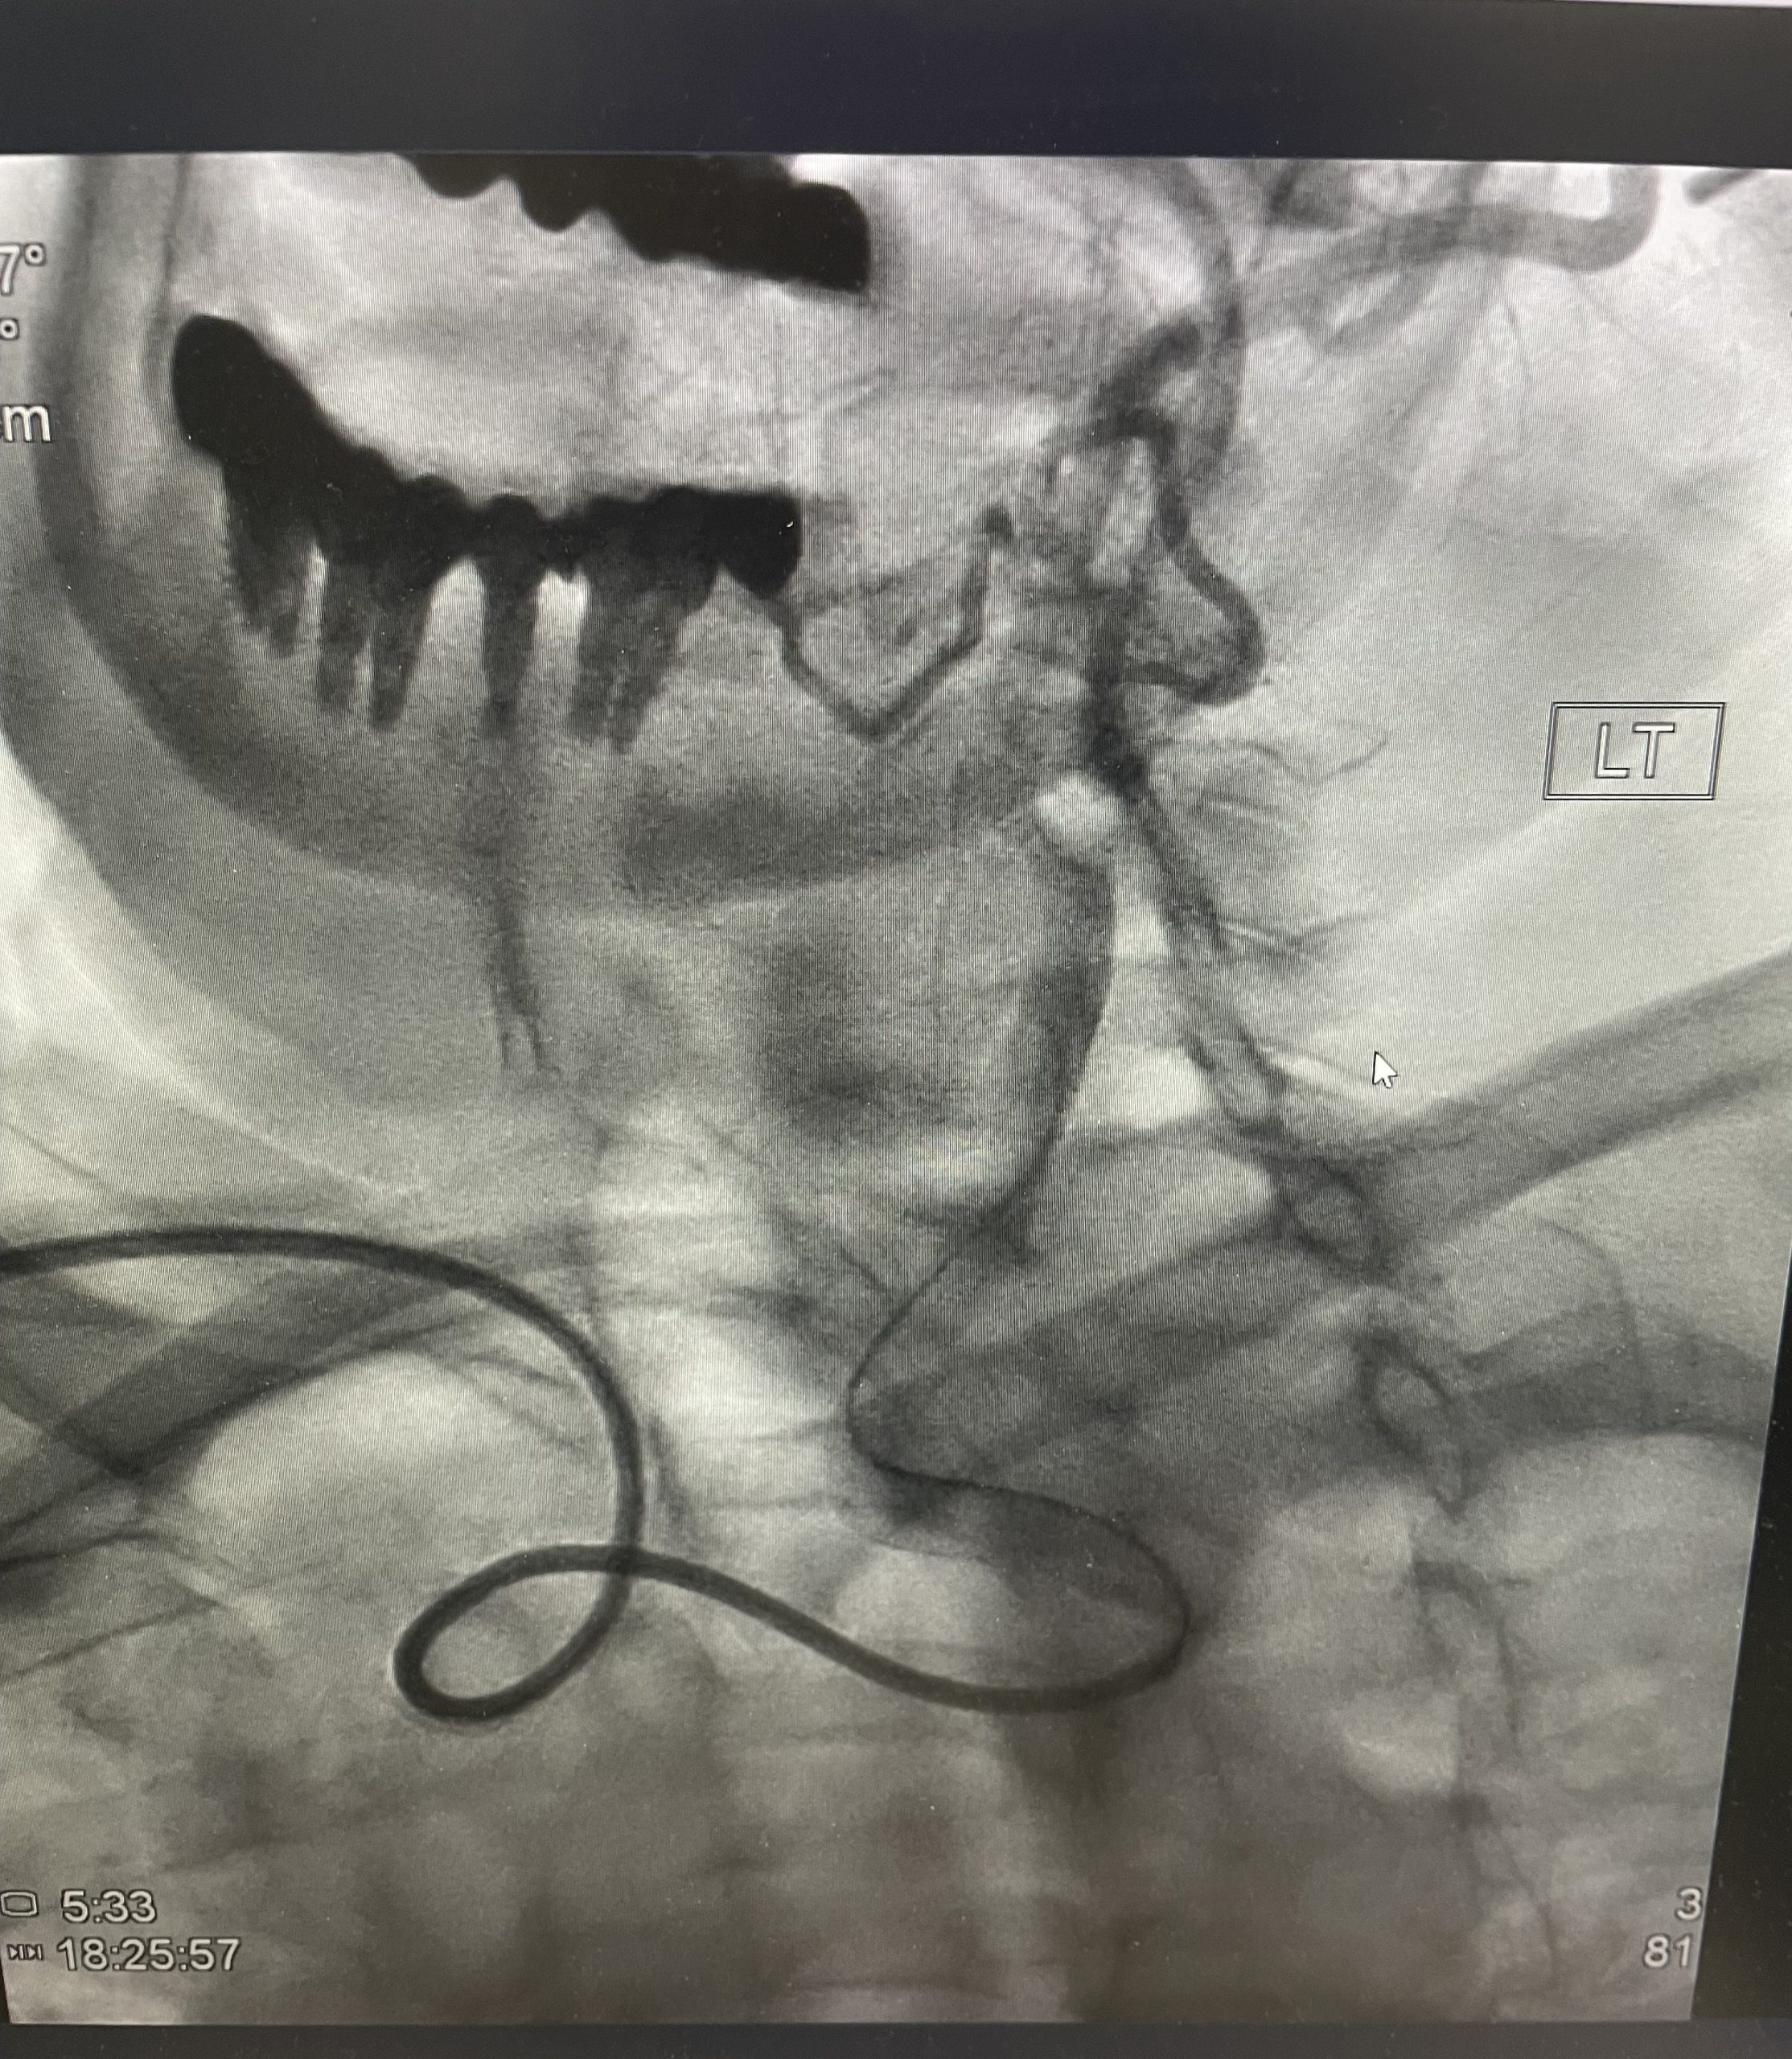

היצרות משמעותית של עורקי הצוואר, אפילו כשהיא “שקטה” לחלוטין (ללא סימפטומים), מהווה גורם סיכון מרכזי לשבץ מוחי איסכמי. ניתוח כלי דם (אנדארטרקטומיה) הוא טיפול יעיל ובטוח, שנחשב במשך שנים רבות לסטנדרט המקובל במטופלים מתאימים, ובמיוחד כאשר יש תסמינים. אולם במסגרת CREST-2 , מחקר שבחן במיוחד מטופלים ללא תסמינים ותוך כדי איזון רפואי מיטבי — נראה כי הניתוח לא סיפק תוספת הגנה מעבר לטיפול שמרני בלבד. לעומת זאת, בחולים דומים, צינתור ופתיחה של ההיצרות עם סטנט, תוך שימוש בפילטר המגן מתסחיפים – הציג יתרון ברור וחד משמעי , בהשוואה לטיפול תרופתי מיטבי, ובניגוד לניתוח כלי הדם.

מחקר ה-CREST-2 נערך ב־155 מרכזים בארה״ב, קנדה, ספרד וישראל, במימון איגוד הרפואה האמריקאי (ללא מימון של חברות מסחריות), וכלל למעלה מ־2,400 מטופלים עם היצרות קרוטיד אסימפטומטית בדרגה של ≥70%. המחקר תוכנן כשני ניסויים מקבילים, אקראיים ועם הערכה סמויה של התוצאים: טיפול רפואי אינטנסיבי לעומת סטנט, וטיפול רפואי לעומת אנדארטרקטומיה. התוצא הראשוני שילב שבץ מכל סוג או מוות בתוך 44 ימים מההתערבות, וכן שבץ איסכמי בצד ההיצרות עד ארבע שנות מעקב. המטופלים היו דומים בכל הזרועות (גיל ממוצע כ־70, כ־40% נשים ושכיחות גבוהה של מחלות רקע), והמעקב כלל הערכה קלינית ונוירולוגית מובנית ובדיקות הדמיה (סיטי ו MRI מוח) לפי צורך, כולל דופלקס עורקים שנתי.

אכן -ההמלצה על יעילות מוגברת של צינתור עורקי הצוואר, קרוטיד, מחייבת הפניה למרכז צנתורים מומחה בעל ניסיון, העושה שימוש רוטיני בפילטר להגנה מפני תסחיף והמסוגל לבצע את פעולה בשיעור סיבוכים נמוך במיוחד.